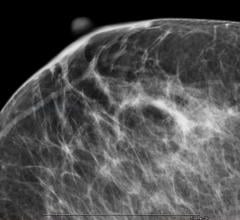

Mammography

Mammography is a breast imaging technique that uses X-rays to diagnose and locate tumors of the breasts.